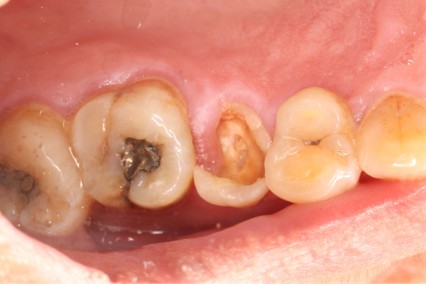

June 20, 2025: The patient's chief complaint is that endodontic treatment was performed on the right maxillary posterior tooth abroad, and a deep carious lesion has been recently detected, requiring restoration. The following are the intraoral photographs taken upon the patient's first visit: a large carious lesion is visible on the occlusal surface of tooth 15 (FDI numbering), with only the buccal wall remaining. Percussion test and cold-hot stimulation test showed no response, and yellow obturation material is visible at the root canal orifices.